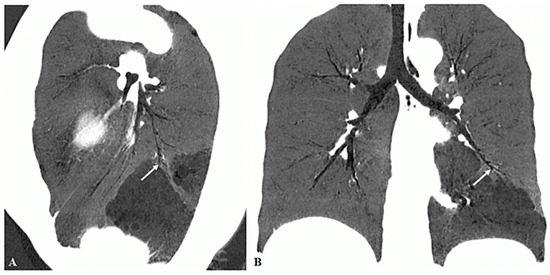

3.2. Imaging Appearances of CTPA